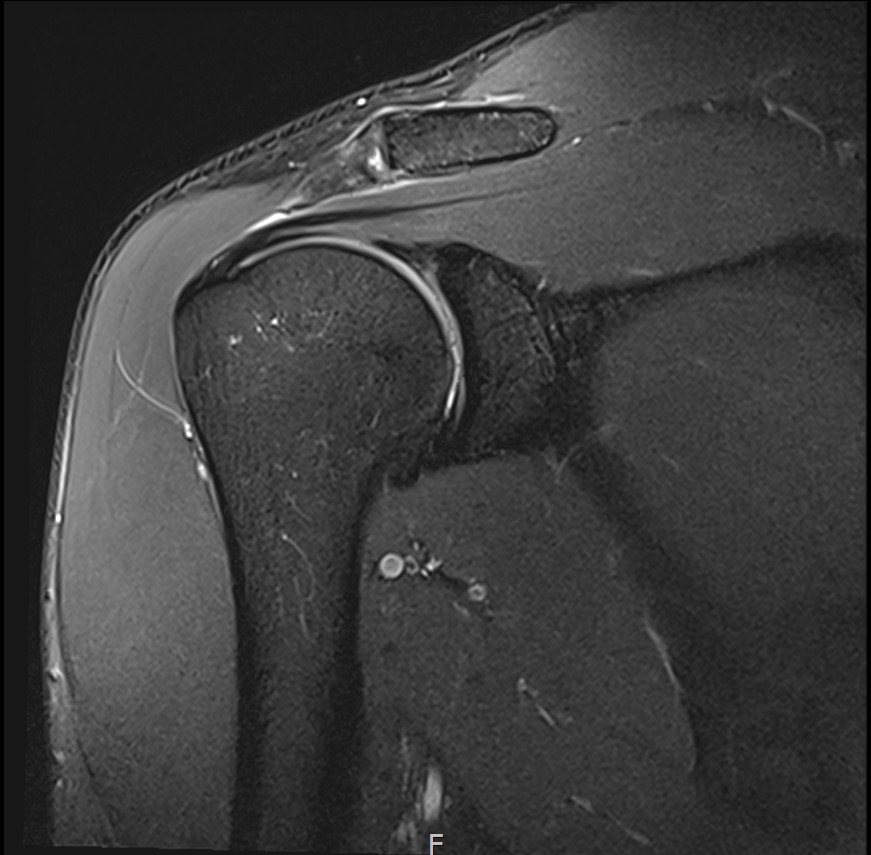

MRI를 검토해보았습니다.

회전근개 극상건의 점액낭면측(bursal-side) 부분파열. 처음보다 파열 범위가 약간 넓어져 있었고, 인대가 얇아진 소견도 보였습니다.

플래티넘의원에서는 MRI와 초음파를 통해 파열 위치를 정확히 판단한 후 치료를 결정합니다.

6개월 후 MRI로 인대 두께 확인